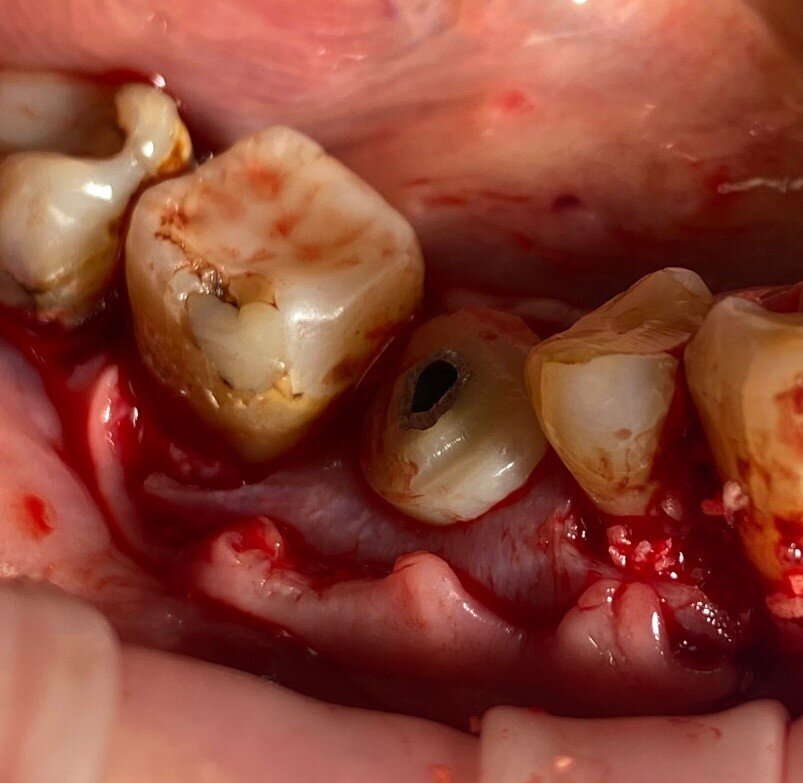

Dopo l’anestesia locale (Articaina con adrenalina 1.200.000), abbiamo utilizzato lo stesso flusso di lavoro chirurgico del caso 1: dopo l’elevazione e il rilascio del lembo su entrambi i lati della cresta, è stato posizionato un impianto MIS V3 con diametro di 4,3 mm e lunghezza di 10 mm (MIS Implants Technologies) subcrestale con il protocollo di espansione Versah con una stabilità primaria di 35 N.cm. Un moncone di connessione con diametro di 5,7 mm e altezza di 2 mm è stato fissato sopra la piattaforma dell’impianto con 30 N.cm. Il sito è stato innestato con osso preparato con l’addizione di SPRF (Process for PRF) e 2 g di osso equino collagenato 0,5 g (Biogen dimensione delle particelle: 0,5-1 mm, Bioteck). Il materiale d’innesto è stato poi coperto da una lamina corticale (Lamina Soft, Osteobiol) montata su un moncone personalizzato realizzato in laboratorio adattato a un cilindro temporaneo da 5,7 (MIS Implants Technologies). La chiusura del lembo è stata ottenuta con i 2 strati di sutura e lo stesso materiale di sutura descritto nella fase 1, e la riduzione della trazione muscolare è stata eseguita con un’incisione superficiale alla profondità del vestibolo, come già spiegato. Le istruzioni post-operatorie e la medicazione erano identiche a quelle del caso 1.

Nel caso 2, il tessuto cheratinizzato è stato preservato anche sui lati vestibolare e linguale a T2 e i valori dell’altezza del complesso sovracrestale erano identici a quelli registrati nel caso 1 (Fig. 26). Per quanto riguarda la valutazione a T3 e dopo l’inserimento di una corona monolitica in zirconia completa a 4 mesi, è evidente che è stata preservata una mimica del profilo cervicale del tessuto molle con conservazione del tessuto cheratinizzato (Fig. 27). Infine, sono state effettuate impronte digitali intraorali utilizzando lo scanner intraorale iTero (Align Technology), a T1 e a T3. I file STL (standard tessellation language) sono stati esportati nel software DTX Studio Clinic (Envista) per la comparazione nel tempo. Sulla base di un algoritmo di informazioni reciproche, le scansioni sono state sovrapposte automaticamente e un codice a colori ha mostrato le aree di differenza (Fig. 27).

Rivalutazione radiologica

La stessa metodologia del caso 1 è stata applicata per il confronto T1-T2-T3. La valutazione è stata effettuata attraverso sezioni trasversali prese nel mezzo del sito sulla sezione assiale e perpendicolari alla cresta alveolare (Figg. 28, 29).